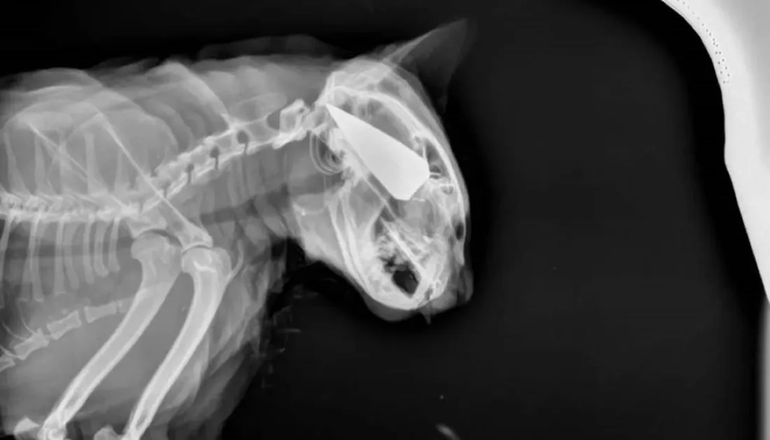

La mascota, de nombre Salem, sobrevivió milagrosamente, dado que apareció con la punta metálica de la flecha incrustada en la cabeza. Todo indica que fue clave la intervención de un médico veterinario.

La información difundida sobre el caso fue acompañada por una foto de una radiografía que muestra el cuerpo metálico dentro del cráneo del animal y otras dos imágenes con la herida de varios centímetros y la restante sosteniendo en su mano el trozo metálico extraído, que revela que tiene gran tamaño dado que le ocupa toda la palma. Según se puede advertir en esta última, se asemeja a las flechas que se utilizan para cazar, un dato que puede ser de utilidad para una eventualidad investigación.